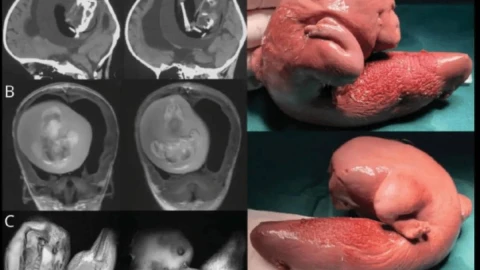

Қыздың ата-анасы баланың басы үлкейіп, моторикамен қиындықтары пайда болғанын байқап, ауруханаға апарады. Нәтижесінде оның миында 10 см-лік ұрық бар екені анықталды.

Дәрігерлердің айтуынша, ұрық өсіп, аяқ-қолдары мен сүйегі, тіпті тырнақтары өскен. Бұл ұрық қан айналым жүйесі мен қыздың қан айналым жүйесінің бірігуіне байланысты болуы мүмкін.

Медицинада “ұрық ішінде ұрық” деген термин бар. Бір ұрық екіншісінің денесінде өседі. Әлемде 200-дей осындай жағдай орын алған. Ұрық ауыз қуысы, жамбас, ішек жолдарында анықталады. Осы уақытқа дейін 18 адамның миында егіз ұрық табылды. Нәрестелерден бөлек, тіпті ересек болған кезде де бұл анықталып жатады.